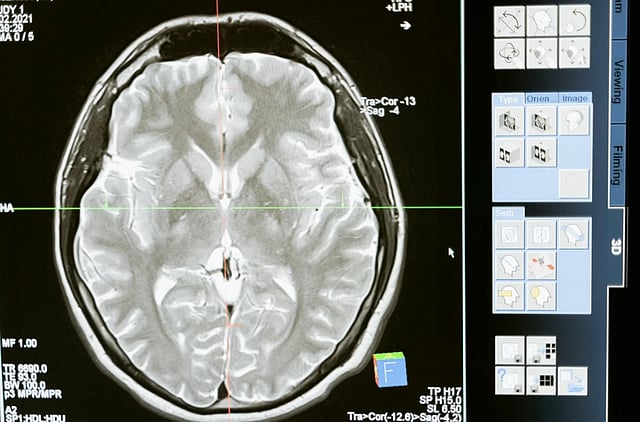

New Delhi, Nov 25: Researchers in Australia have found that Parkinson's disease causes significant and progressive changes in the brain's blood vessels, changing the understanding of the disease.

While Parkinson's disease is characterised by alpha-synuclein protein deposits, the research demonstrated that region-specific changes to blood vessels in the brain underlie disease progression, Xinhua news agency reported.

"Traditionally, Parkinson's researchers have focused on protein accumulation and neuronal loss, but we have shown the impacts on our cerebrovasculature -- the blood vessels in our brain," said Derya Dik, postdoctoral student at Neuroscience Research Australia (NeuRA).

"Our research identified region-specific changes in the brain's blood vessels, including an increased presence of string vessels, which are non-functional remnants of capillaries," Dik added.

NeuRA researchers, in collaboration with the University of New South Wales and the University of Sydney, also observed changes relating to how blood flows in the brain and how the blood-brain barrier operates.